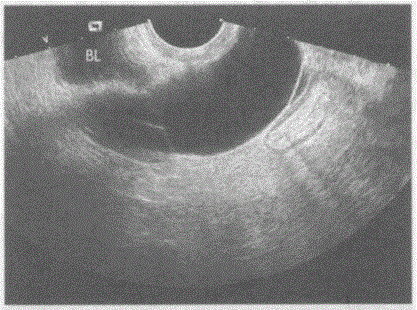

问题 临床资料:女,41岁,子宫全切术后。妇科内诊:盆腔可触及肿物,质软。 超声综合描述:经阴道扫查左附件区可见腊肠样无回声区,内透声清亮。 超声提示:

选项 A.左输卵管积水 B.左卵巢囊肿 C.左卵巢冠囊肿 D.盆腔包裹性积液

答案 A